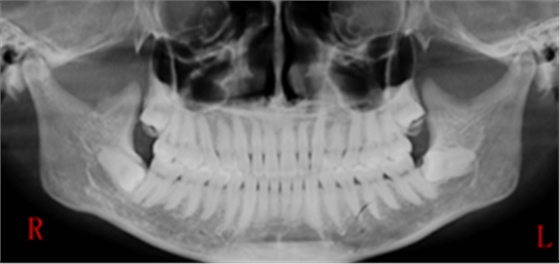

右下智齒去骨范圍如何?分冠線如何?怎樣才能最快時(shí)間能把這顆牙拔出來(lái)?

答:本x線片示48近中低位埋伏阻生,且牙根緊鄰下牙槽神經(jīng)管,拔除時(shí)需注意充分去除近中方向的牙體冠方阻力及遠(yuǎn)中的牙槽骨阻力,挺出牙根時(shí)盡量做到一次完成,減少牙根與神經(jīng)管的摩擦,降低神經(jīng)受損風(fēng)險(xiǎn)。

遠(yuǎn)中:骨阻力 近中:牙體冠方組織

第一:確定阻力去骨的范圍: